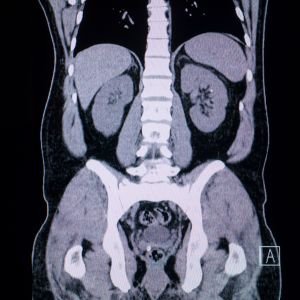

Abdomen & Pelvis CT Scan

Used for detecting tumors, infections, and gastrointestinal issues, this scan offers clear, non-invasive internal views.